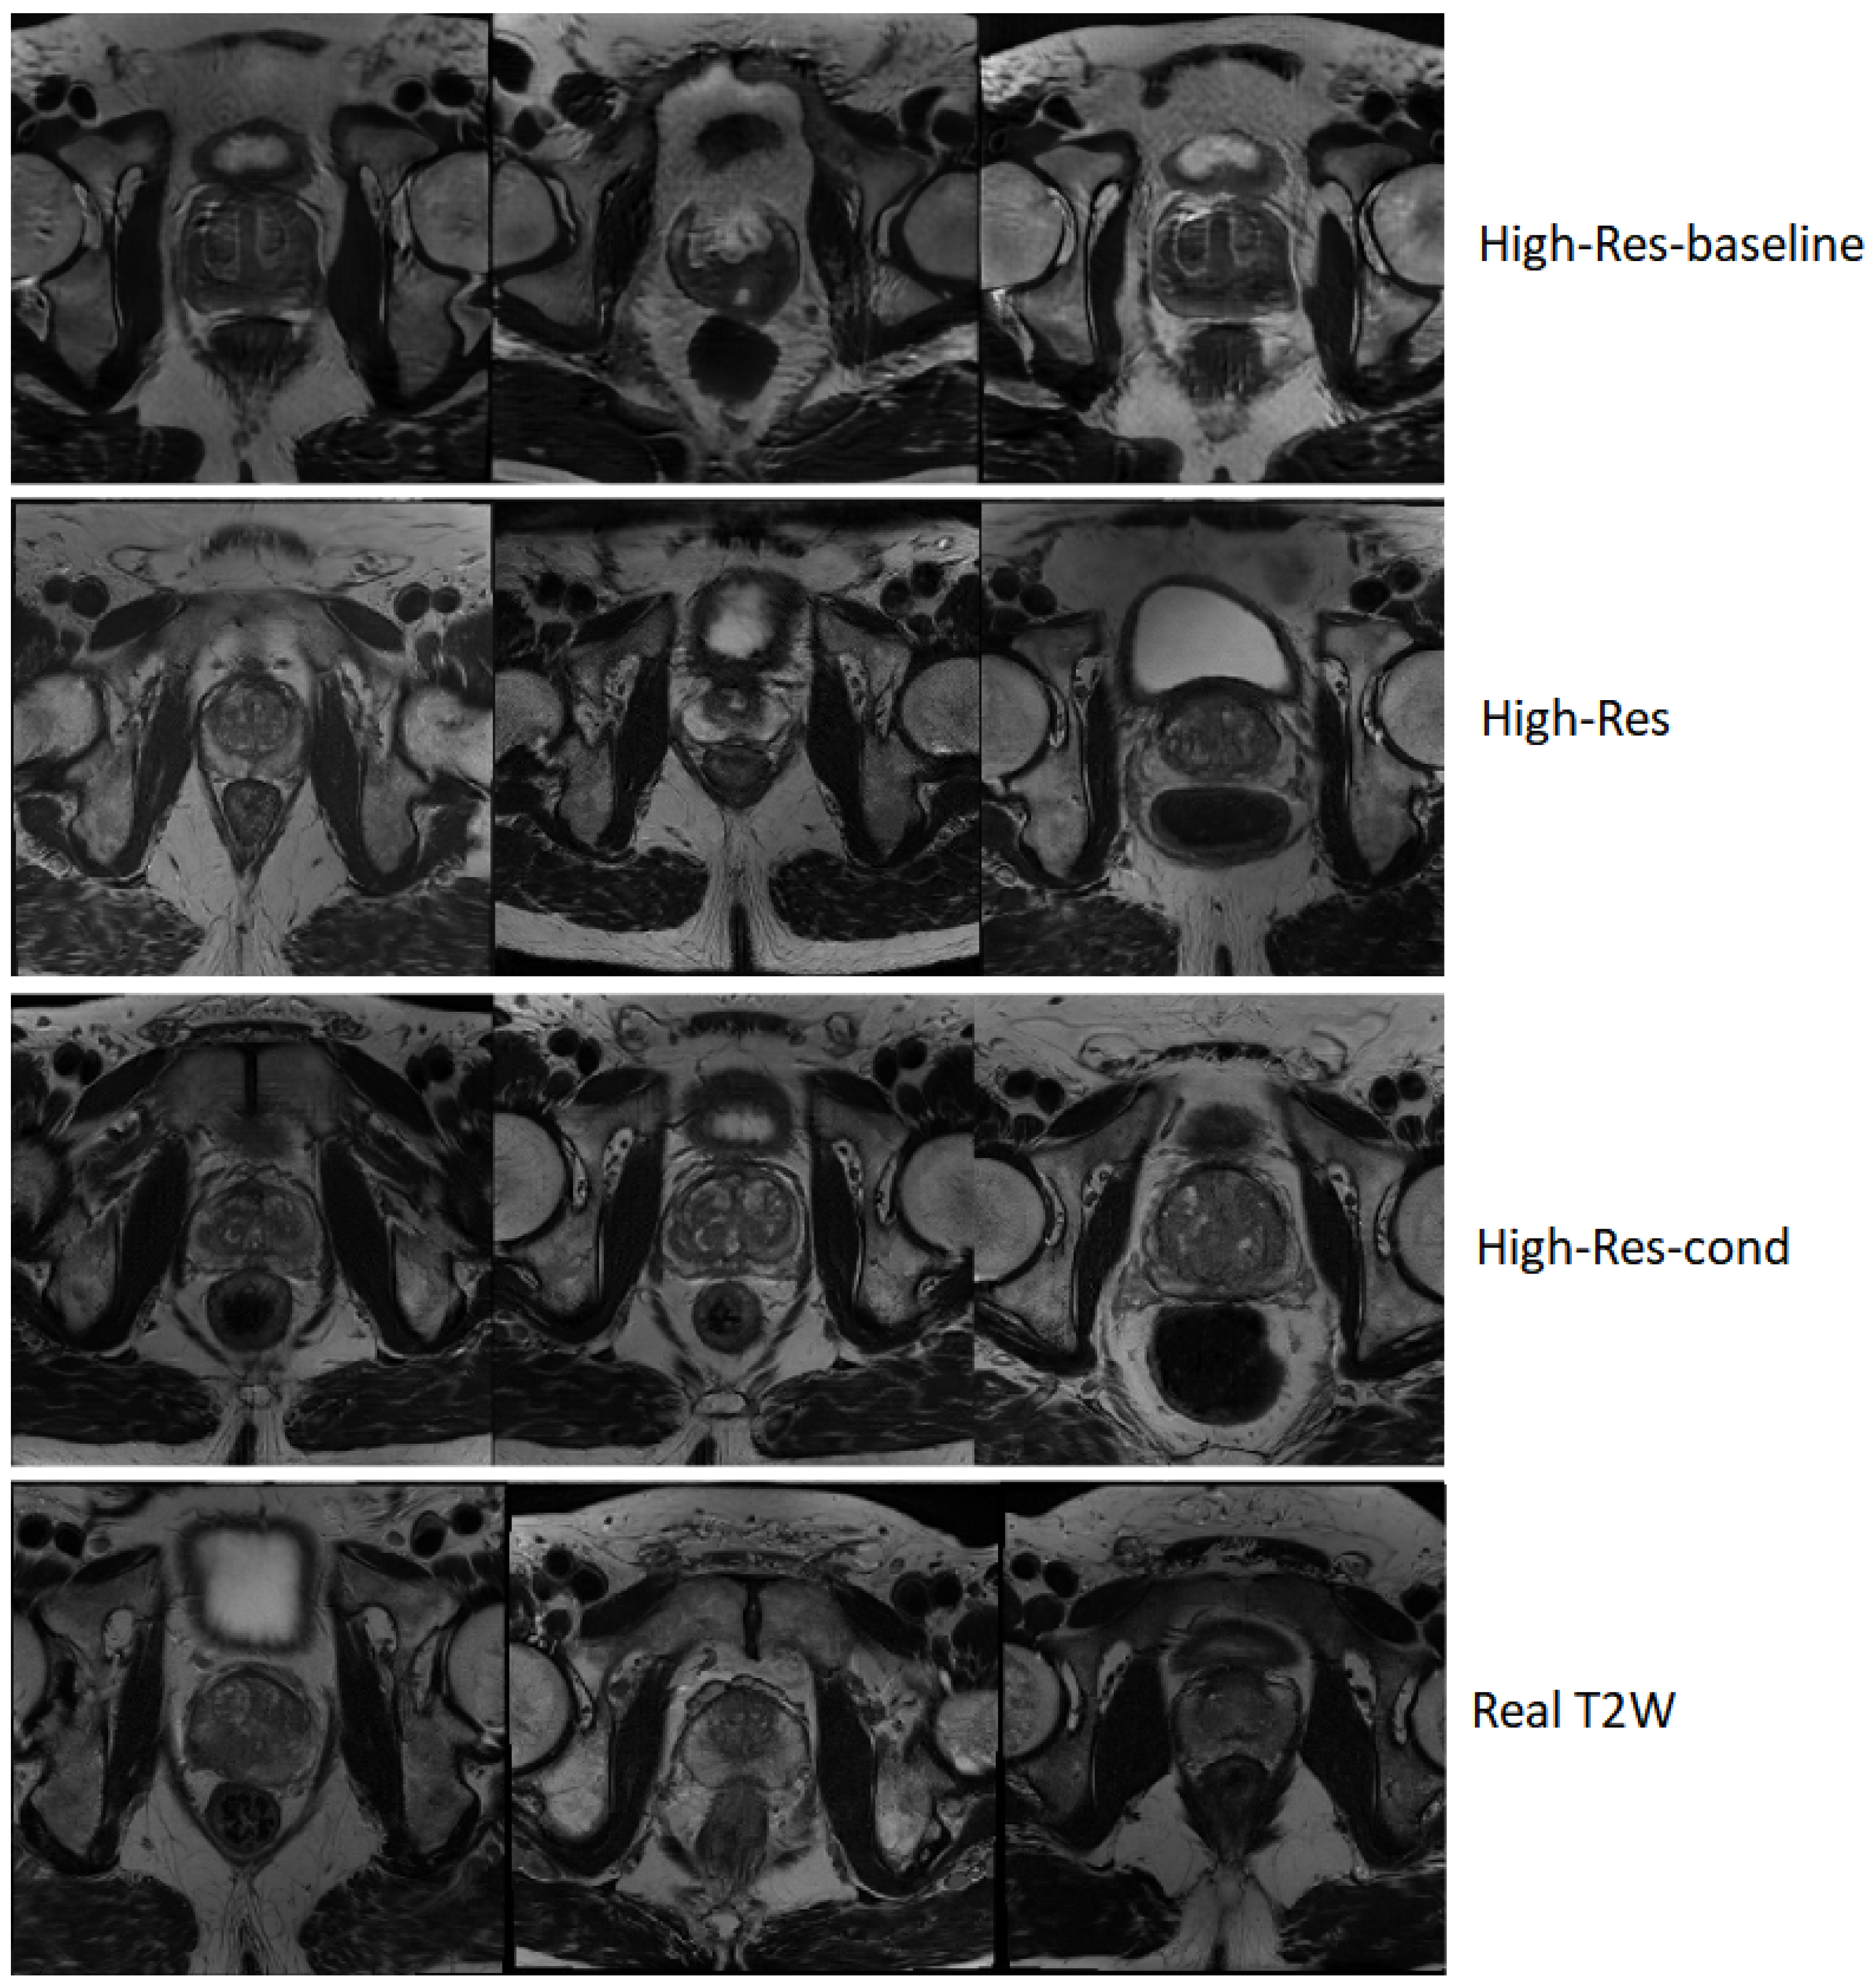

A qualitative comparison of samples generated by the three models is presented in Figure 2. The figure contrasts representative axial slices from the baseline and the ADA-based models against real T2W volumes. The High-Res-baseline samples exhibit visibly unrealistic anatomical structures, irregular gland boundaries, and inconsistent internal texture patterns that deviate from real prostate morphology. In contrast, both ADA-based models generate anatomically coherent gland shapes, plausible zonal structure, and realistic soft-tissue contrast. Differences between the unconditional and conditional variants are minimal in terms of perceptual image quality, consistent with the quantitative metrics.

Figure 2. Qualitative comparison of axial T2W slices generated by the models at 256 × 256 × 24 resolution. The baseline model images exhibit anatomically inconsistent gland structures and irregular texture patterns, whereas both ADA-based variants produce anatomically coherent prostate morphology and realistic soft-tissue contrast comparable to real data.